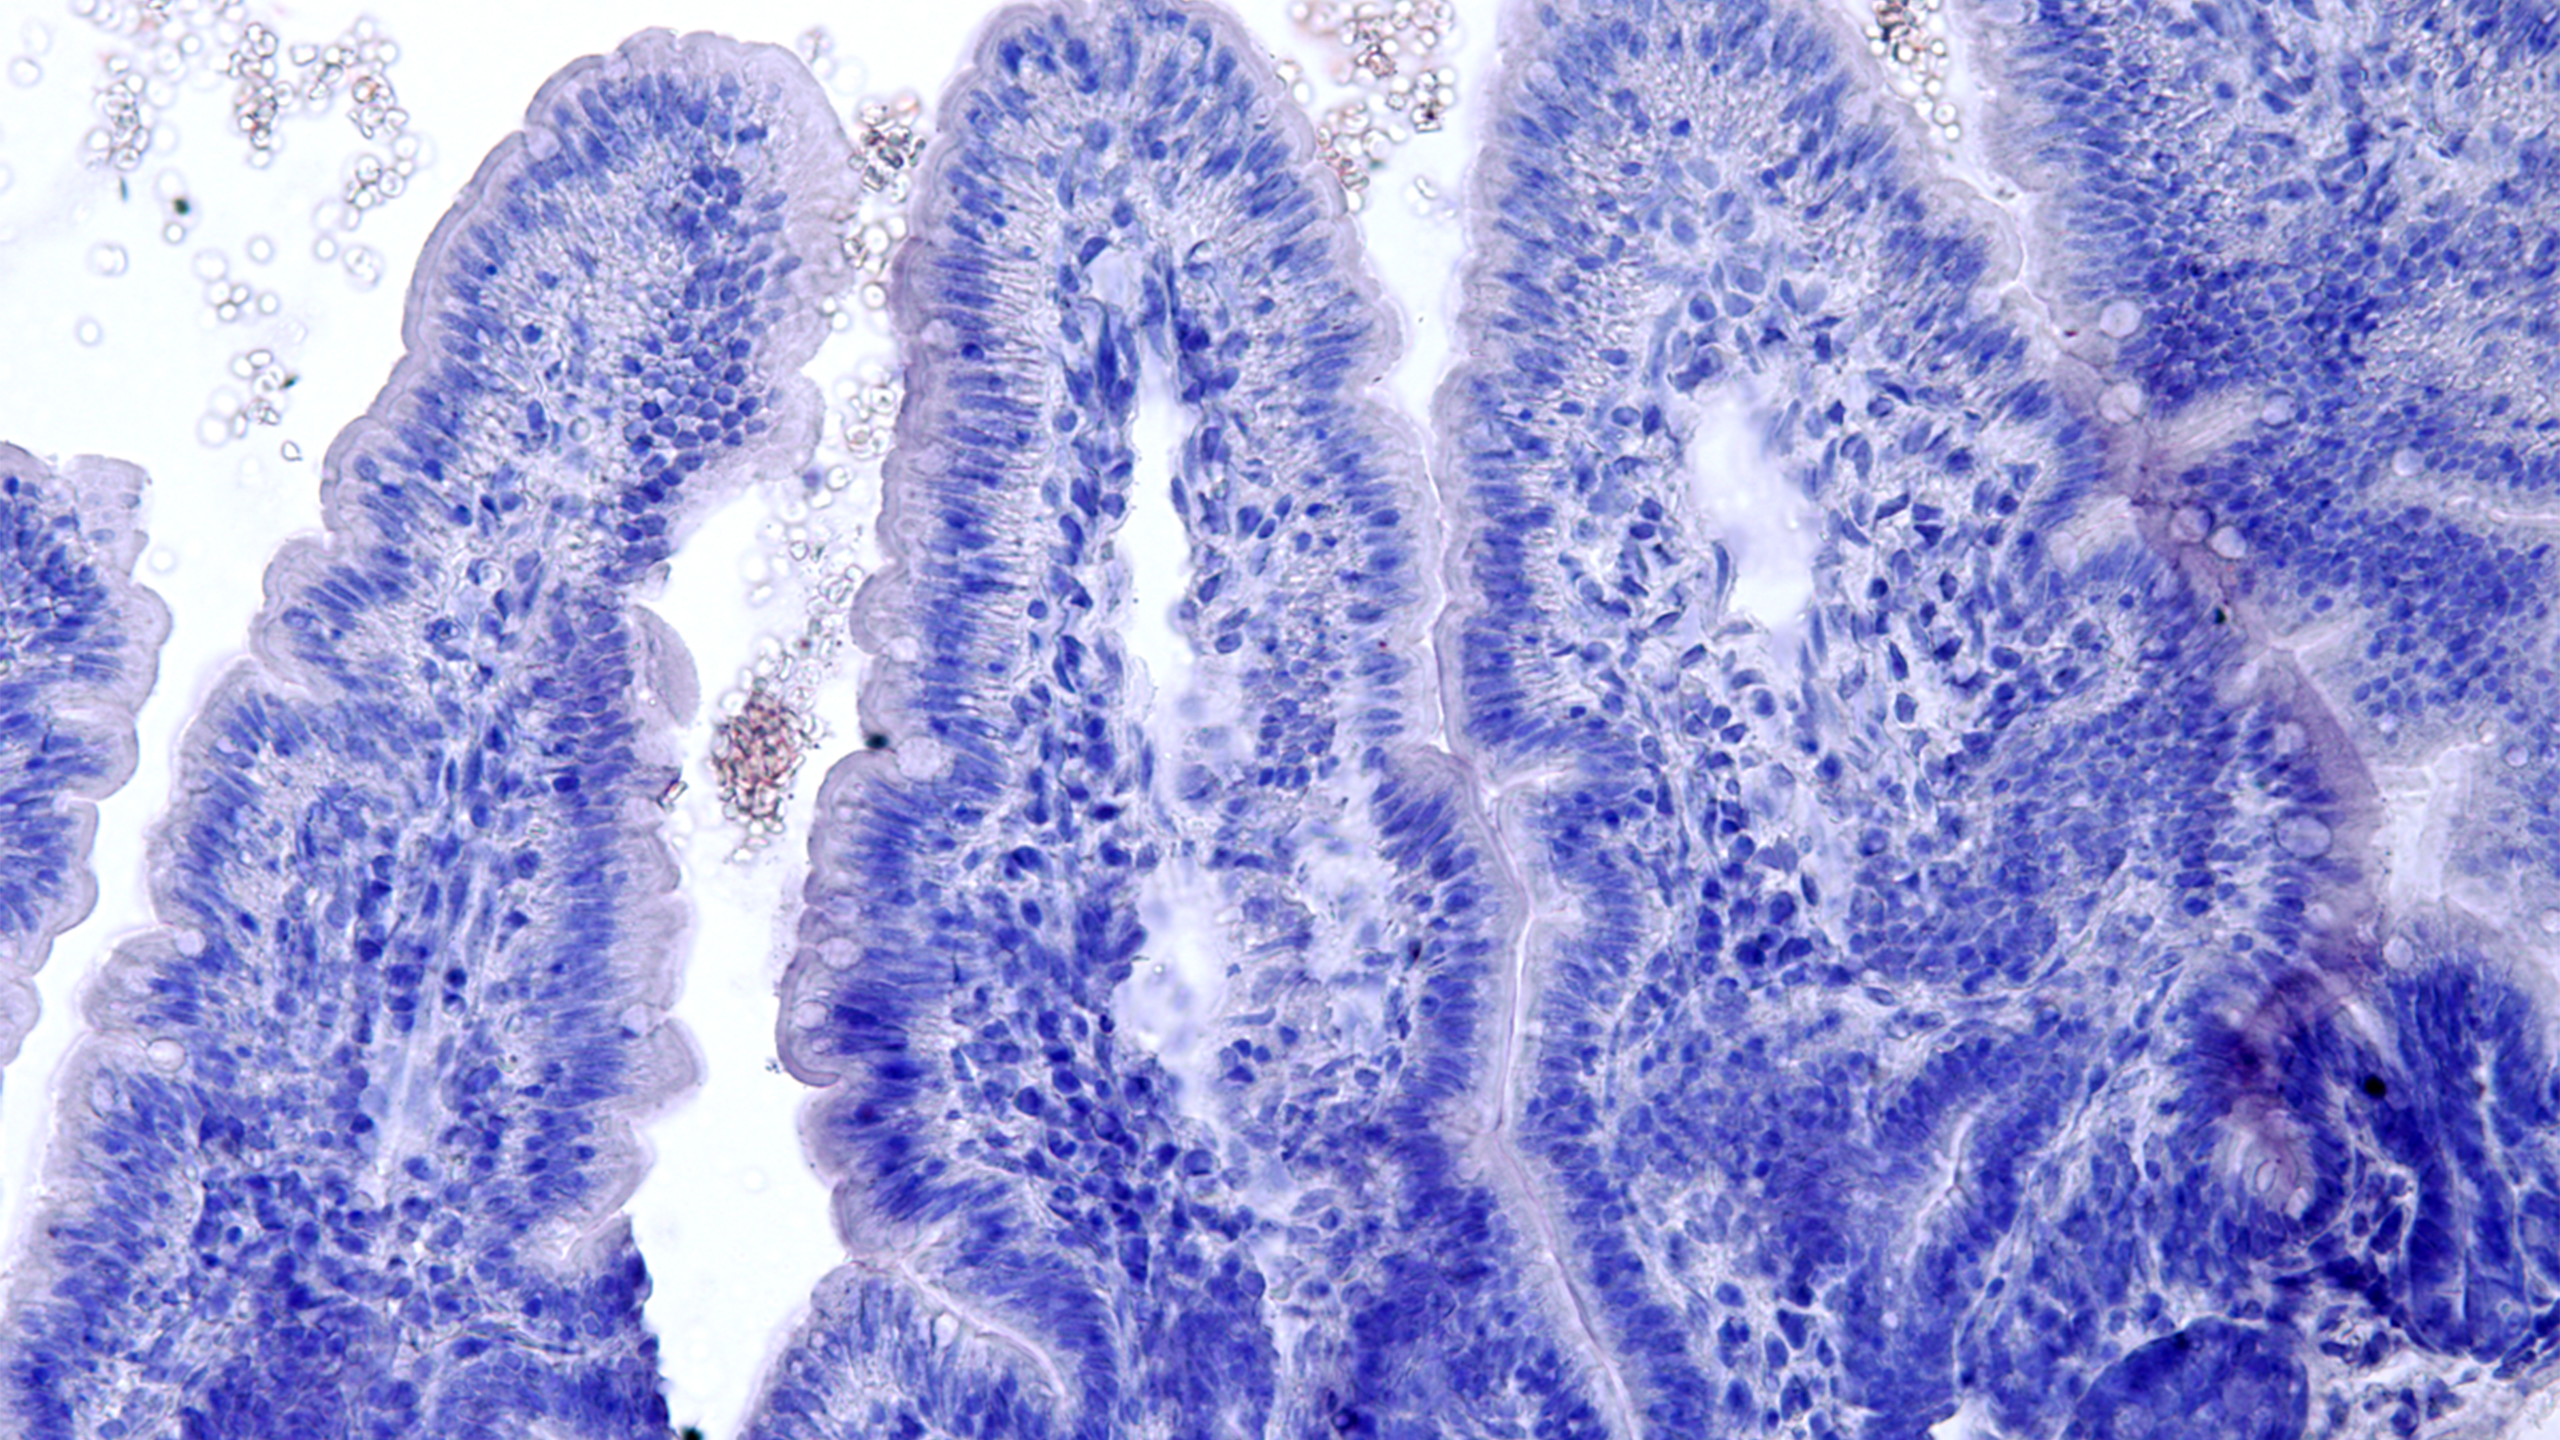

Image: Andrea Puhar lab

Mechanism and inflammatory impact of extracellular ATP signaling in intestinal bacteria

The project aims at understanding how extracellular ATP-dependent signalling in commensal and pathogenic gut bacteria impacts the development of intestinal inflammation.